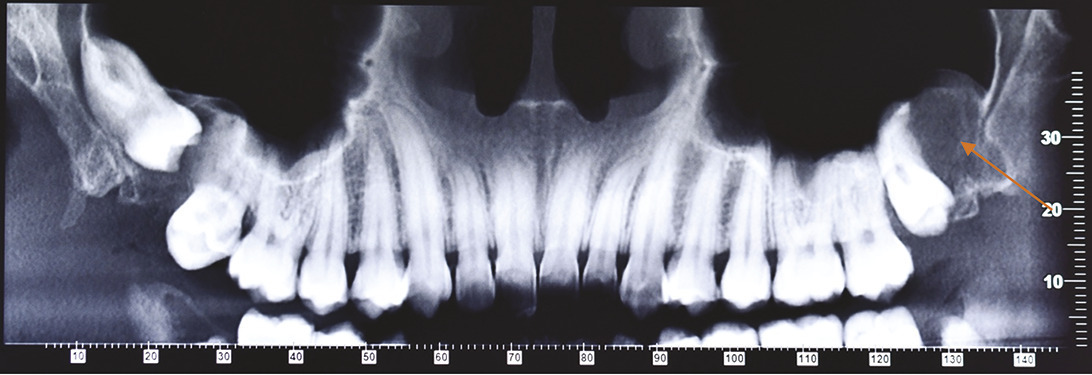

Cette femme de 26 ans consultait pour des douleurs récidivantes au niveau des dents de sagesse. Elle avait comme antécédents un asthme et une néphrectomie du rein droit en raison d’une dysplasie. Sa consommation tabagique était estimée à 6 paquets-année. Le panoramique dentaire (fig. 1 ) montrait quatre images radioclaires entourant les dents de sagesse. La patiente était alors adressée dans le service de chirurgie où un Cone Beam (fig. 2 et 3 ) permettait d’évaluer la taille des lésions kystiques ainsi que leurs rapports avec les structures anatomiques voisines. L’avulsion des dents de sagesse et l’énucléation des kystes étaient réalisées. L’examen anatomopathologique des lésions notait une paroi kystique bordée par un épithélium malpighien ortho- ou parakératosique avec une hyperplasie des couches basales compatible avec des kératokystes bénins odontogènes.